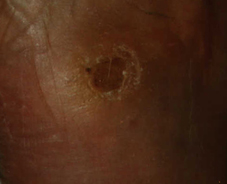

Passage of a sequestrum at the right midfoot planto-lateral. Formation of a 2.5 cm deep cavity, that is irrigated with Lavasept.

Insertion of a Septopal mini chain until 1998/07/06. Afterwards daily insertion of a sterile LIGASANO® white pack, soaked with Ringer´s solution. For pressure distribution supply with a neuropathy-adapted cast.

Another visit in our ambulance at 1998/07/17. The cavity is only 5 mm deep, no signs of inflammation. At 1998/09/23 complete closure of the lesion.